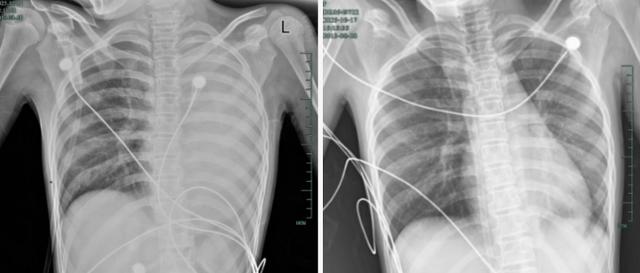

治療前後影響對比,左肺從“白肺”到正常狀態。

呼吸急促、胸悶胸痛,體溫38.5℃,只能靠 5L/min 的面罩吸氧維持血氧,胸片顯示左肺已完全呈 “白肺” 改變,肺部炎症進展迅猛。